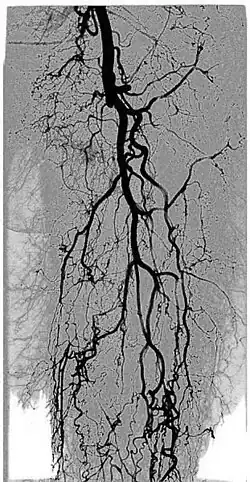

Kinetic image or DVA (digital variance angiography) of a patient's leg, obtained from previously acquired fluoroscopic angiography data. Movement of a bolus of contrast agent allows visualization of the blood vessels.

By allowing visualization of movements, kinetic imaging offers a new type of motion-based contrast. In many cases, the kinetic image will have a higher SNR (better image quality) compared to traditional images for moving objects.[2][6][1][3][4]

This improvement in SNR and image quality has been studied by Gyánó M. et al. (2018)[3] and Óriás V. et al.(2019)[4] in the field of traditional angiographic imaging and carbon-dioxide imaging. Their findings indicate that by using the kinetic imaging (or as they called this method in the case of angiographies, digital variance angiograpy, DVA) for processing angiographic image sequences, the quality improvement may increase diagnostic insight and it also creates a quality reserve, which means that DVA could provide the same level of image quality, as the gold-standard DSA technique, but the dose of administered radiation and/or contrast agent could be lowered.[3]

The kinetic image may allow visualisation of physiological movements, such as pulsing of the aorta, passing of a contrast agent bolus in the arteries, movement of the thoracic diaphragm, inflation and deflation of the alveoli in the lungs, or the constantly moving gastrointestinal tract.